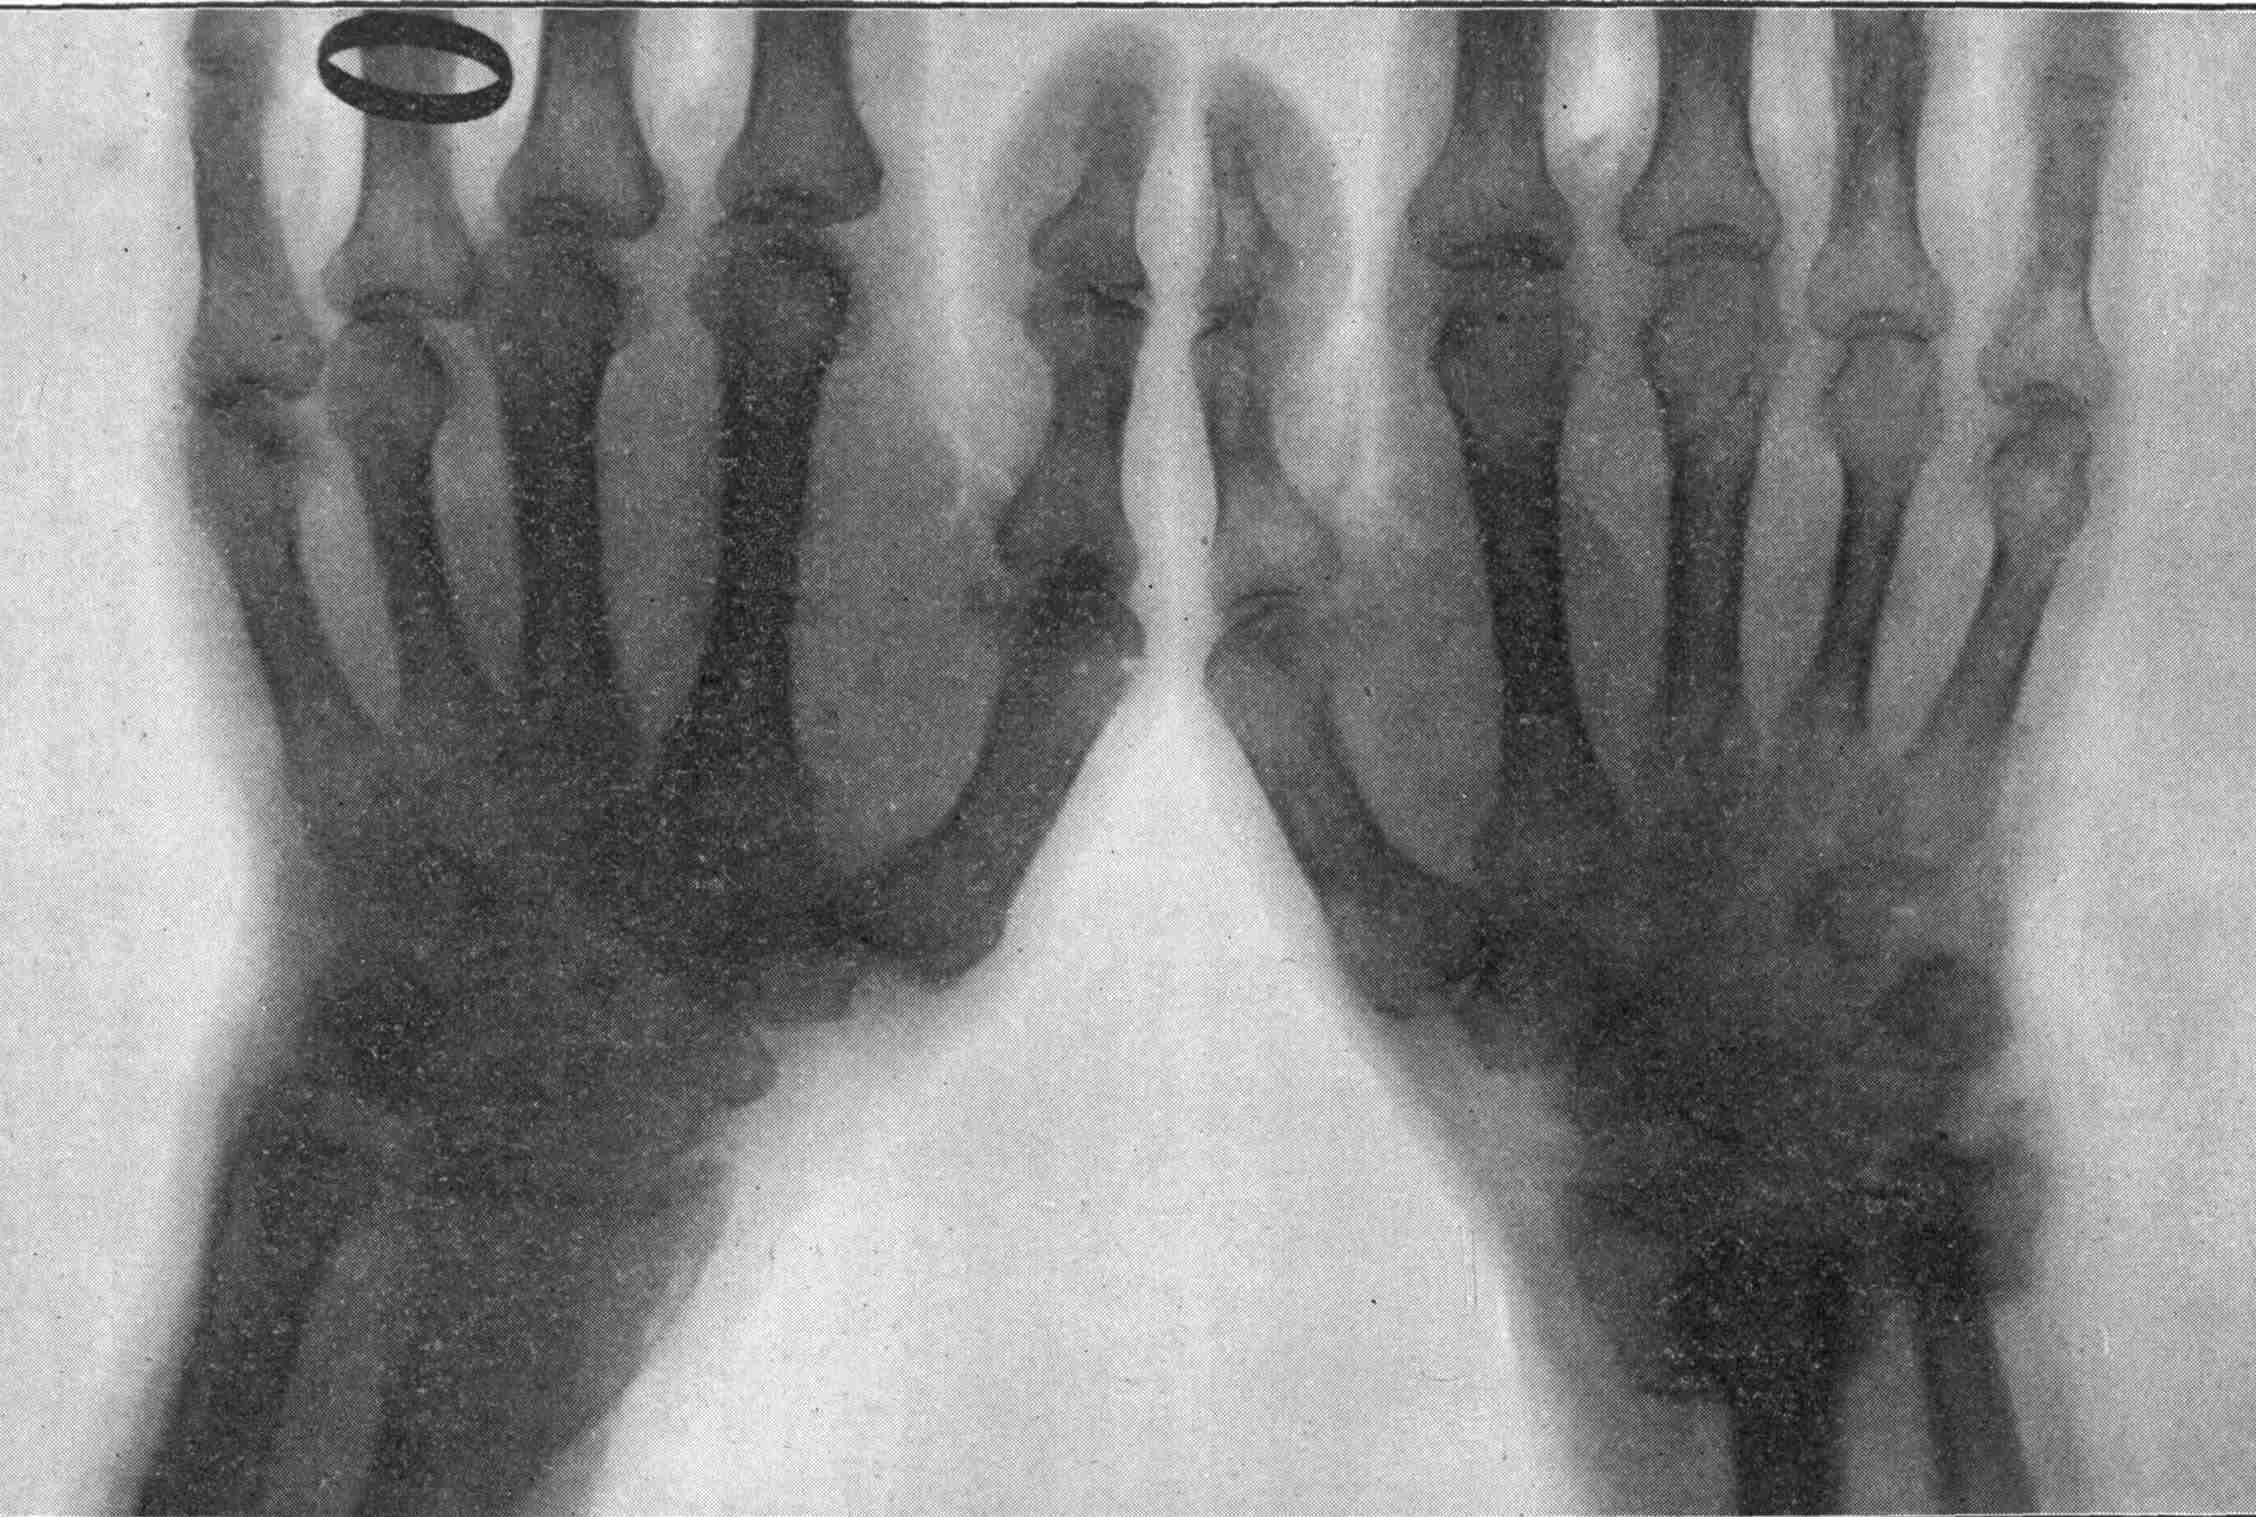

Fig. 2.—Broken Arm, Overlapping.

(Due to defective setting.)

FROM SCIAGRAPHS BY PROF. DAYTON C. MILLER. § 204.

117. Transposition of Phosphorescent Spot and of Cathode Rays without a Magnet. Salvioni, Elster, Geitel, and Tesla